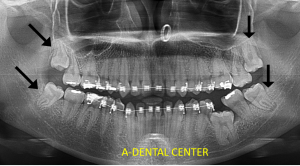

Dental X-rays in North Hollywood reveal what clinical examination simply cannot. They show several critical things that would otherwise go completely undetected:

- Impacted, unerupted, or problematic wisdom teeth — often completely asymptomatic until they cause damage to adjacent teeth

- Infections or cysts at the root tips of teeth — detectable only through imaging

- Root fractures and other structural issues — frequently missed without X-ray confirmation